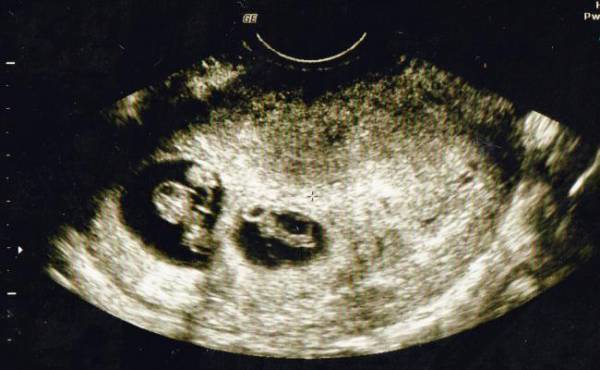

エコーで確認すると3人分の心拍が!

私が3人目を妊娠したのは長男が3歳、次男が1歳のときでした。そろそろ赤ちゃんの心拍が確認できるかな? なんて期待を胸に抱きながら、内診台でエコーを見ていると見覚えのある袋が2つ? その中には心拍のように動いて見えるのが3つ?

私が混乱していると、先生が「お母さん。赤ちゃん何人か見える?」と聞いてきました。先生と一緒に確認し、見事に3人の心拍を確認! パニックで笑うことしかできず、頭のなかは真っ白で少しの間その場から動けませんでした。